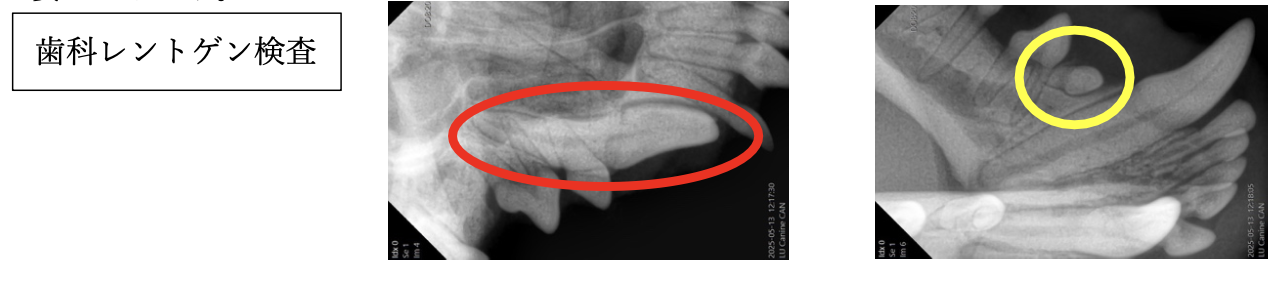

歯科レントゲン検査で歯肉の下に隠れている歯(埋伏歯・まいふくし)の有無を確認する必要があります。

右上顎犬歯(赤丸)と右下顎第一前臼歯(黄色丸)が埋伏歯であること、その他の歯は生まれつきないことがわかりました。